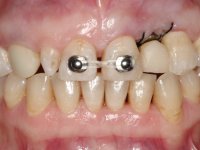

Treatment began with re-preparation of the cast post and core, with the purpose of placing the cervical finishing lines with an intra-sulcular location and simultaneously making a suitable temporary crown. With a very simple orthodontic treatment, the diastema was closed between the upper central incisors, and this position was stabilized with a wire placed on the palatal surface of the central, functioning as containment. Later, a slow orthodontic traction of tooth 2.2 was attempted, in order to reduce, although very slightly, the vertical bone loss in this area. At the end of the traction, tooth 2.2 was extracted and the area was provisionally rehabilitated with a composite resin crown bonded to the adjacent teeth. A dental implant was placed in the area of tooth 2.2 and the temporary crown was again bonded to resin, provisionally rehabilitating the patient during osseointegration. In tooth 1.3 a gingivectomy with an electric scalpel was performed, with the intention of raising the cervical level of 1.3 achieving greater harmony with tooth 2.3. Stabilized soft tissues were impressed using the open tray technique with putty and light addition silicones. Collection of the color of both the dental component and soft tissues was done by the ceramist in the office. In the laboratory, the impressions were transferred to plaster and gave origin to work models that were properly analyzed. It was decided to assemble a metal-ceramic abutment screwed onto the implant. This abutment was cast with a noble alloy and subsequently coated with coronary and gingival ceramics. Due to the inclination of the implant, the screwing inevitably conditioned the exit of the screw hole through the vestibular surface. In order to conceal this situation, the design of the abutment has already been conceived with the intention of accommodating on the vestibular surface the bonding of a feldspathic veneer. This abutment was tested in the mouth and adjustments were made in the gingival ceramic component. Its adaptation to the soft tissues was done in a subtractive way, with a drill, as well as additive, adding resin composed of gingival tonality.

This addition of resin would guide the ceramist in the final placement of the gingival tonality ceramic. The crown that would rehabilitate tooth 1.3 was cemented in this test session with glass ionomer cement, reinforced with composite resin. Once the laboratory work was finished on the veneer for tooth 1.2, the abutment, and the veneer for the implant, this was bonded in the mouth, after placement of the absolute insulation. The work completely satisfied the patient. For eight years, the patient had periodical check-ups, and was pleased with the treatment, but also began to show interest in an aesthetical intervention on the upper central incisors. Once the second phase of our intervention was decided, dental preparation of teeth 1.1 and 2.1 was performed for the placement of two feldspathic veneers. Particular care was taken in the distal inter-proximal preparation adjacent to the abutment of the implant.